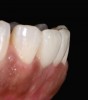

A patient in her 60s wanted to improve her smile but declined orthodontic treatment in favor of porcelain veneers (Figure 13). However, addressing her 8-mm pocket was the first step. The practitioner created biologically clean root surfaces using ultrasonic open-flap debridement, finishing burs, and manual tool instrumentation. Next, a mineralized freeze-dried bone allograft saturated in platelet-derived growth factor (Figure 14) using chemotaxis pulled the stem cells capable of regeneration into the site where repopulation was needed. Prior to closure, a resorbable membrane, polylactic acid-guided tissue regeneration—known for periodontal regeneration—was used (Figure 15). At 10 weeks, adequate healing had occurred. The patient at 6 and 10 weeks showed continued healing. Although some postoperative recession was evident, probing depths were less than 2 mm, and the patient was referred back to the restorative dentist for restorative therapy. As of this writing, she has not lost any teeth and is periodontally stable (Figure 16).

Growth-factor hydrated freeze-dried bone allograft.

Figure 14